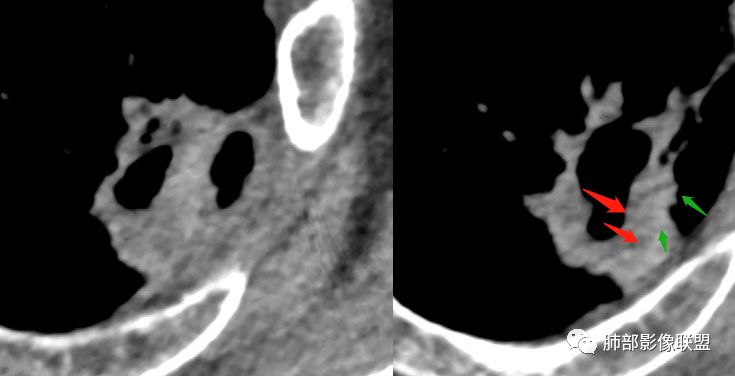

1.左肺上叶应为空腔样病灶。如作为空洞,前下壁并不完整,且与薄壁囊腔壁相延续,整体结合起来看应为厚薄不均匀的较大的空腔样病灶。这样的空腔样病灶应首先怀疑空腔性肺癌。

2.厚壁区可见壁结节及液化坏死。图像未能完整显示小支气管情况,但空腔的存在提示与支气管或多或少还是相通的。

3.病灶轻度环形强化,壁稍显僵硬。灶周显示较清楚,未见磨玻璃晕。

2.空洞壁厚薄不一,超过15mm恶性居多。

3.内壁凹凸不平。换个视角说,有壁结节,外缘呈分叶状。

4.支气管常截止病灶处,且不会行走厚壁间。

5.轻度或中度环形强化,坏死区不强化。由于破坏性强,加之癌肿生长过快,肿瘤组织压迫供血血管,导致血管阻断、狭窄、血液供应内壁不足,缺血坏死,所以腔壁强化偏弱。